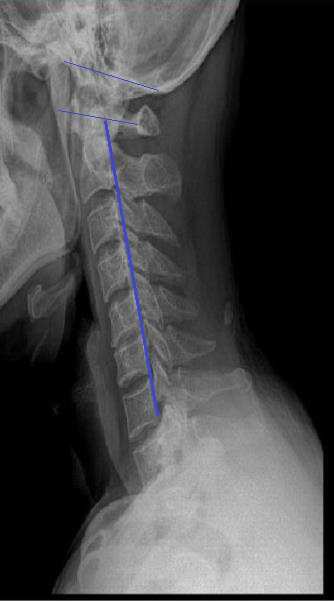

거북목을 치료 한다고 목을 억지로 잡아당겨 집어 넣은 동작은 목을 일자로 만드는 게 아니라 너무 지나쳐서 도리어 목을 앞으로 꺾는 동작입니다. 디스크 주변의 인대가 약화되고 손상되어 디스크가 만성적으로 악화 될 수 있습니다.

일자목은 잘못된 체형 중 대표적인 것이지만 단순히 근육을 풀어서 해결할 수 있는 문제는 아니며 흔하게 소개되는 운동 방법들 중에는 문제가 될 수 있는 동작들도 적지 않습니다.

좋은 체형이란 보통 허리와 목 부분의 S자 모양의 자연스러운 만곡을 제외하고 수평적이고 수직적인 척추 위에 두개골(머리)이 균형 잡힌 채로 서 있는 것으로 이해된다. 반대로 나쁜 체형은 척추 전체가 과도한 S자형이거나 C자형이고 이런 척추 위에 머리와 어깨가 앞으로 쏠려 있게 되는 자세를 보통 말한다.